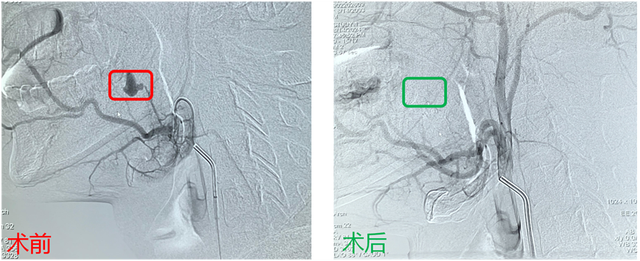

结合小李的情况,青大附院市南院区介入科徐锐主任团队立刻着手制定手术方案,由该团队的赵晓龙医生对患者进行口底假性动脉瘤栓塞手术。术中,主刀医生赵晓龙通过穿刺右侧股动脉,置入6F血管鞘搭建通路,在颈外动脉造影的帮助下,成功发现了出血部位——上颌动脉的小分支上可见一个假性动脉瘤正随着血管搏动,随后通过组织胶进行栓塞。整个手术过程仅用时半个小时左右,止血效果立竿见影。术后,小李惨白的脸色渐渐红润起来,住院一天后顺利出院。